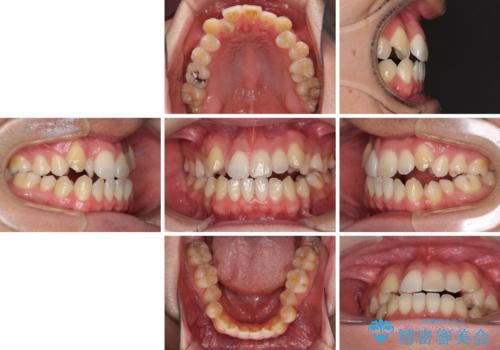

左右の八重歯が気になる ワイヤー装置での咬み合わせ改善

- 30代男性

- 八重歯と前歯のデコボコを気にして来院された患者様です。

営業職であり、商談などで飲食をする機会が多いとのことで、インビザラインではなく、ワイヤー装置にて矯正治療を行うこととしました。